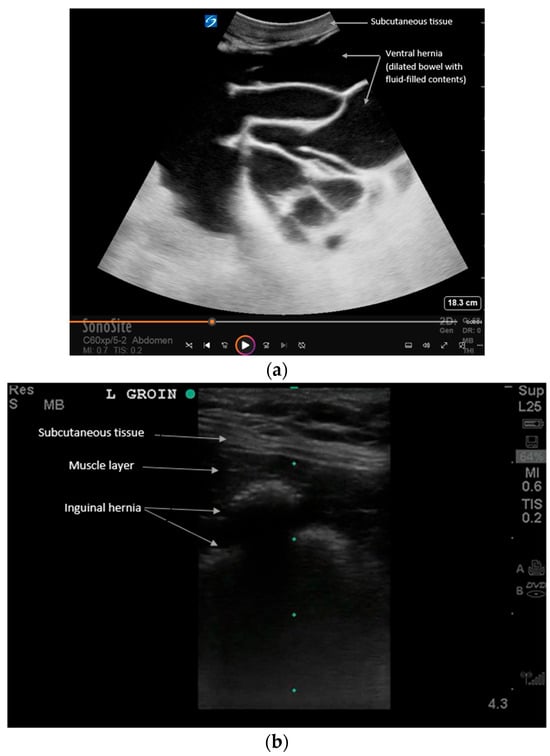

Figure 3.

Examples of (a) ventral and (b) inguinal hernias that contain loops of bowel on POCUS. See Supplementary Videos S2 and S3 for examples of dynamic findings. Intestinal hernias can be evaluated with ultrasound at the bedside for faster recognition and manual reduction. Ultrasound reveals loops of bowel traversing the abdominal wall muscles. Dynamic assessment with Valsalva is recommended per expert consensus to evaluate reducibility and complications [11]. For example, the patient can be asked to perform a Valsalva maneuver to exaggerate the hernia during real-time ultrasound. Increased vascular flow, extra-luminal fluid, bowel dilation, or wall thickening can all suggest an increased risk for hernia incarceration or strangulation, which requires expedited treatment. Also, the lack of peristalsis within the bowel is a sign of complication [18].